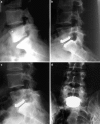

A retrospective clinical-radiological study to evaluate the long-term outcome after artificial disc replacement was performed. The objective is to investigate long-term results after implantation of a modular type artificial disc prosthesis in patients with degenerative disc disease (DDD). Total disc replacement (TDR) is a surgical procedure intended to save segmental spinal function, and thus replace spondylodesis. Short-term results are promising, whereas long-term results are scarce. The Charité TDR is the oldest existing implant, therefore, the longest possible follow-up is presented here. Seventy-one patients were treated with 84 Charité TDRs types I-III. Indication for TDR was moderate to severe DDD. Fifty-three patients (63 TDRs) were available for long-term follow-up of 17 years. Evaluation included Oswestry disability index, visual analog scale, overall outcome score, plain and extension/flexion radiographs. Implantation of Charité TDR resulted in a 60% rate of spontaneous ankylosis after 17 years. No significant difference between the three types of prostheses was found concerning clinical outcome. Reoperation was necessary in 11% of patients. Although no adjacent segment degeneration was observed in the functional implants (17%), these patients were significantly less satisfied than those with spontaneous ankylosis. TDR, nowadays, is an approved procedure. Proof that long-term results of TDR implantation in DDD are at least as good as fusion results is still missing.